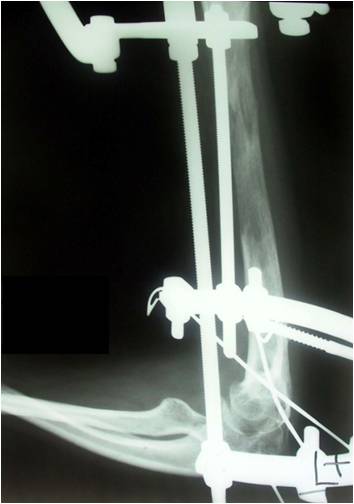

Blount disease is a developmental disorder characterized by disordered growth of the medial aspect of the proximal tibial physis resulting in progressive lower limb deformity. The deformity consists of varus, procurvatum, and internal rotation of the tibia, However, in the advanced stage of the disease, there is a bony bridge formation with medial plateau depression, joint instability, and leg length inequality, all of which have to be addressed by the proposed treatment. We treat this case by intra atticular osteotomy to elevation of medial plateau and another metaphyseal osteotomy to correct the varus and internal rotation deformities.

داء بلونت يطلق علي اعوجاج الساق المكون من هبوط باعلي الجزء الداخلي من اعلي عظمه الساق مع اعوجاج انسي بالساق و يتم علاج تلك الحالات بواسطه شقين عظميين احدهما خلال غظروف اعلي عظمه الساق والاخر بالجزء العلوي للساق مع الاستعدال التدريجي بواسطه مثبت خارجي مع العلم ان العلاج لا يرتبط بوزن المريض حيث يتم عمل العمليات بنجاح في الحالات السمنة الشديدة كما هو موضح بالصور